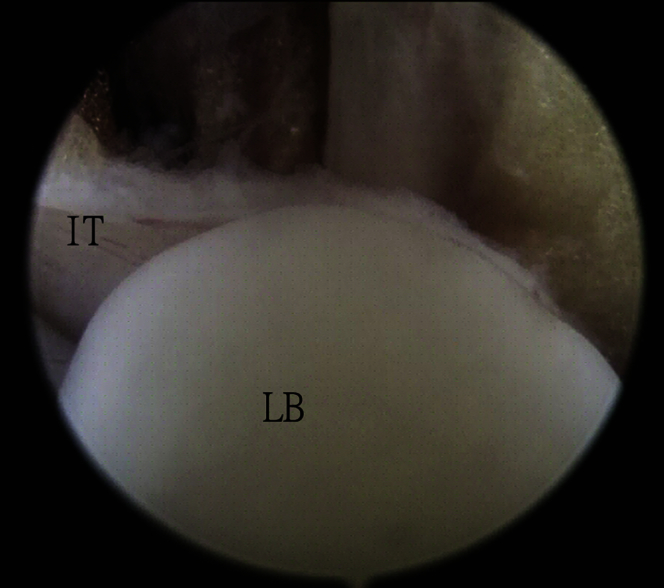

After clearance of zone 1, zone 2 FHL tendoscopy is performed. The ankle is positioned in slight plantar flexion to relax the neurovascular bundle during zone 2 FHL tendoscopy. The FHL tendon is traced distally to the fibro-osseous orifice at the posterior talar tubercle. A Wissinger rod (Dyonics) is inserted through the posteromedial portal into the zone 2 tendon sheath under the sustentaculum tali. The rod passes through the tendon sheath and pierces through the plantar aponeurosis. There should not be any resistance during passage of the rod before the aponeurosis is reached. This can reduce the risk of injury to the tendons and neurovascular structures of the sole by the rod. The plantar portal incision is made at this point, and the rod exits through the plantar portal (Fig 2). Loose bodies are usually trapped by the interconnection tendon of the master knot of Henry (Fig 3). To facilitate access to the master knot of Henry, the aponeurosis should be penetrated at a point distal to the level of the navicular.13, 14

Fig 3.

Zone 2 tendoscopy of the right foot with the patient in the prone position. The posteromedial portal is the viewing portal. A loose body (LB) is trapped by the interconnection tendon (IT) at the master knot of Henry.